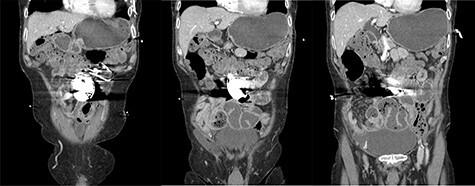

Adhesive small bowel obstruction (ASBO) is commonly caused by intra-abdominal adhesions, usually from prior surgery. Conservative management is the mainstay of treatment, with adhesiolysis required for non-resolving obstruction. An unusual patient presentation of ASBO is presented here, where the cause is proposed as an automatic implantable cardioverter defibrillator (AICD) within the abdomen. Although the patient had several presentations of ASBO successfully treated with conservative management, a non-resolving obstruction required surgical management. At laparotomy, the AICD was found to be in close association with extensive matted adhesions to adjacent small bowel. Adhesiolysis was performed, with the AICD implanted in a subrectus pocket. The patient had an uncomplicated recovery, and at review 6 weeks following the operation was found to have a normal bowel habit with nil further episodes concerning for obstruction. This case highlights the importance of non-classical risk factors being a possible cause of ASBO.

https://cdn.ncbi.nlm.nih.gov/pmc/blobs/8719/8478473/5d54ff6171e5/rjab423f1.jpg